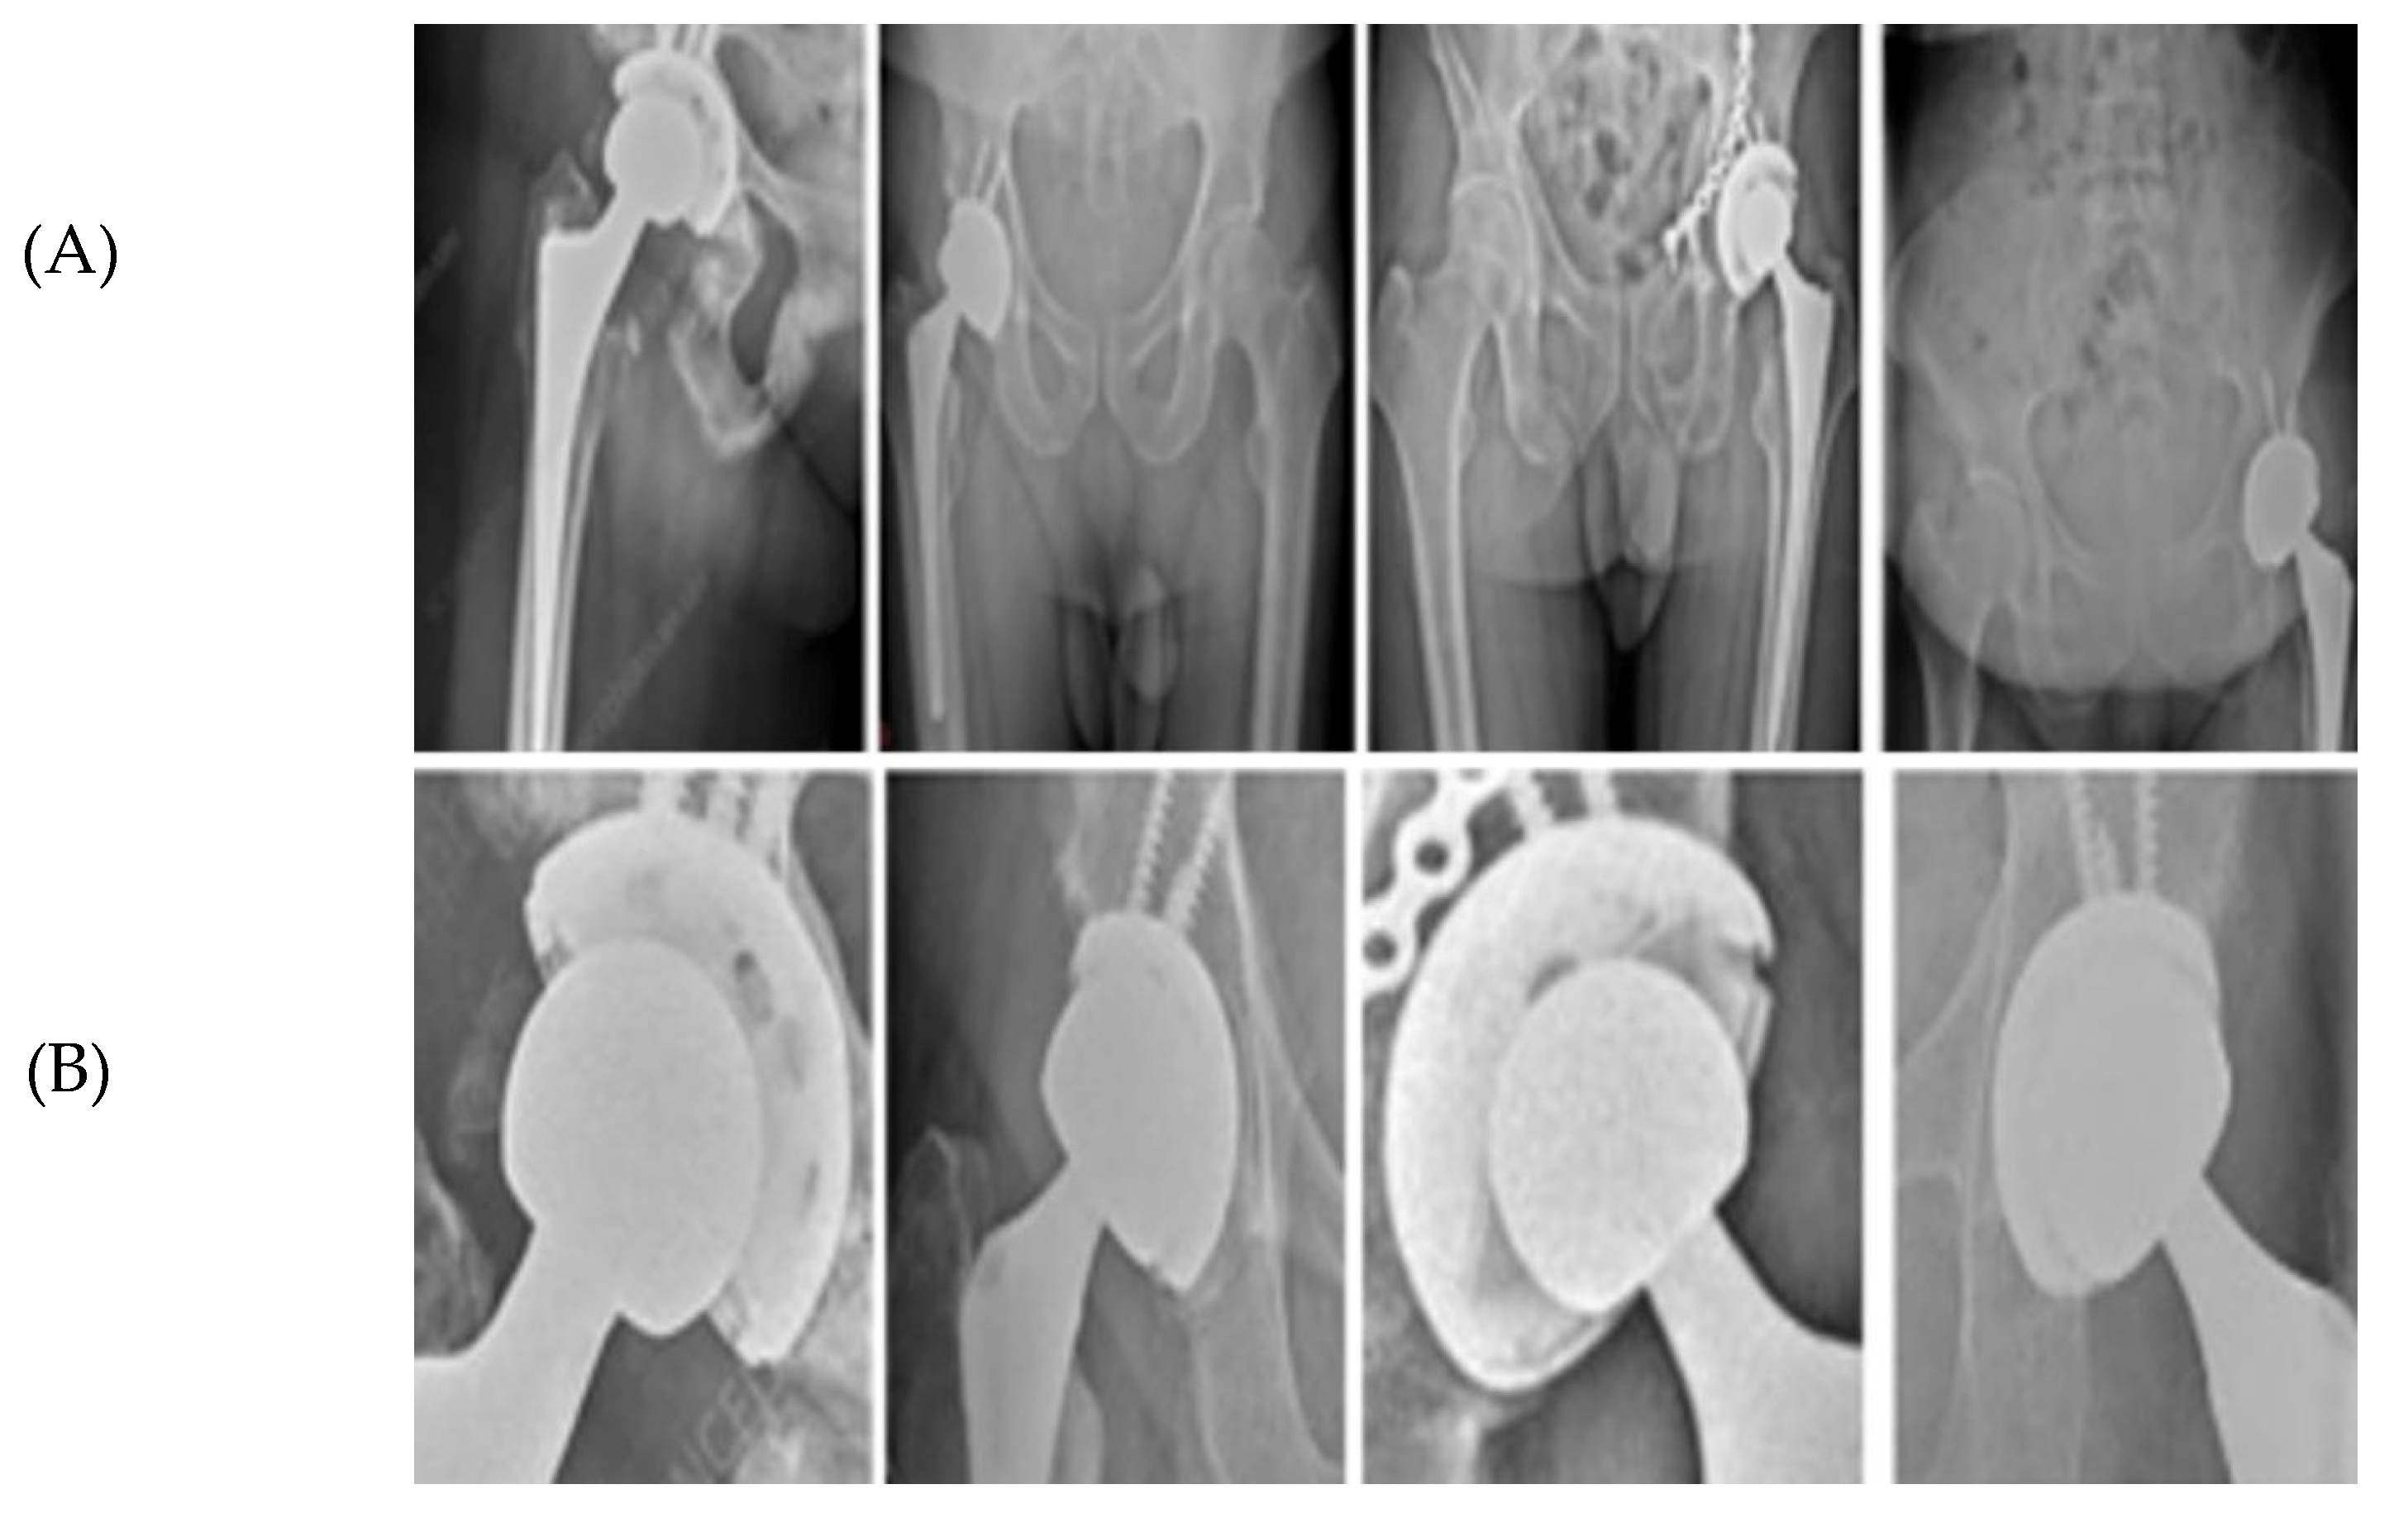

YOLOv5 was employed as an initial localization module to extract a coarse ROI encompassing the hip prosthesis, as illustrated in Figure 3. Unlike standard multi-class detection pipelines in which bounding boxes directly represent femoral head or AC locations, the detector in this study was configured to identify the prosthesis region as a whole. The output of this stage is therefore a single, high-confidence ROI bounding the implant complex rather than individual anatomical components.

Figure 3.

ROI extraction from hip prosthesis X-rays. (A) AP pelvic radiographs containing a hip prosthesis. (B) Automatically extracted Regions of Interest (ROIs) generated by the YOLOv5 localization stage. Each ROI corresponds to the model’s predicted implant region and is forwarded to the subsequent edge-based refinement and circle-fitting pipeline (RANSAC and Hough-based detection). This step ensures that only implant-focused, anatomically relevant regions are processed during circle estimation.

This ROI is subsequently cropped at full resolution and passed to the circle-refinement pipeline (Section E), where component-level delineation is performed. Within the ROI, candidate femoral head and AC circles are generated using RANSAC-based fitting, with a Hough-transform fallback for cases of insufficient edge continuity. All candidates are then subjected to Canny-based edge validation and anatomically constrained filtering to ensure geometrically and biomechanically plausible selection of the final two circles. In this framework, the ROI serves purely as a spatial prior that restricts the search space, while the accurate identification of the femoral head and AC is achieved exclusively through the model’s geometric refinement stages.